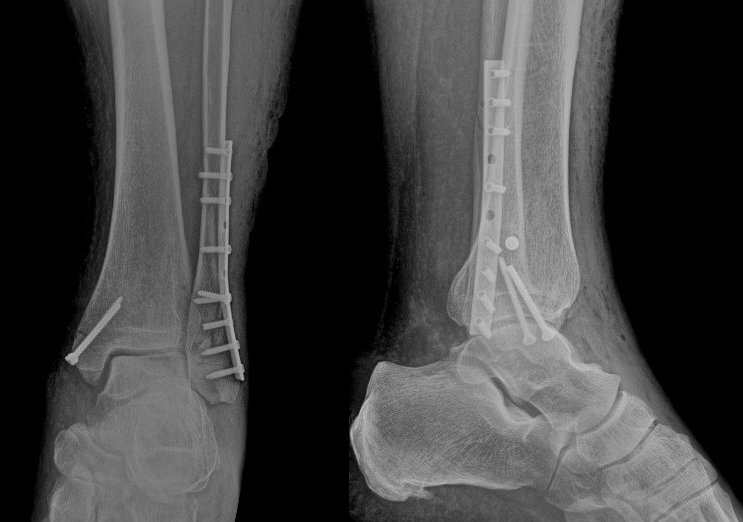

Вечер четверга, около 19.00, как вдруг в палату приходит медбрат и начинает передвигать кровати – чтобы везти пациента на рентген. Я поинтересовался, почему так поздно? Оказалось, что у рентгенолога было настолько много работы, что очередь травматологии подошла только теперь. (На самом деле пациента стоило бы перекладывать на каталку, везти его на кровати крайне неудобно и тяжело. Но как переложить человека с кровати на каталку в одиночку, да ещё со сломанной ногой?) Снимок сделан, кровать с пациентом вернули в палату, медбрат ушёл.